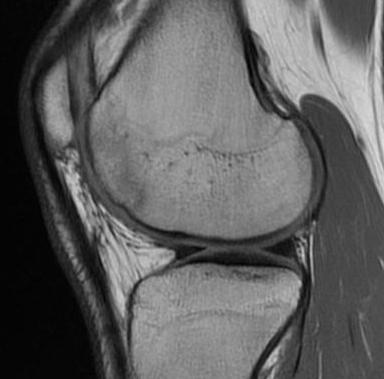

Stable lesion with no cysts Stable lesion with cysts

Progression of reossification over 6 months following drilling